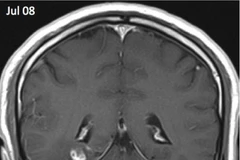

Các nhà nghiên cứu cho rằng người phụ nữ này bị nhiễm bệnh sau khi chạm hoặc ăn phải những loài rau gần nhà được cho đã nhiễm trứng giun thải ra từ chất bài tiết của một con trăn.